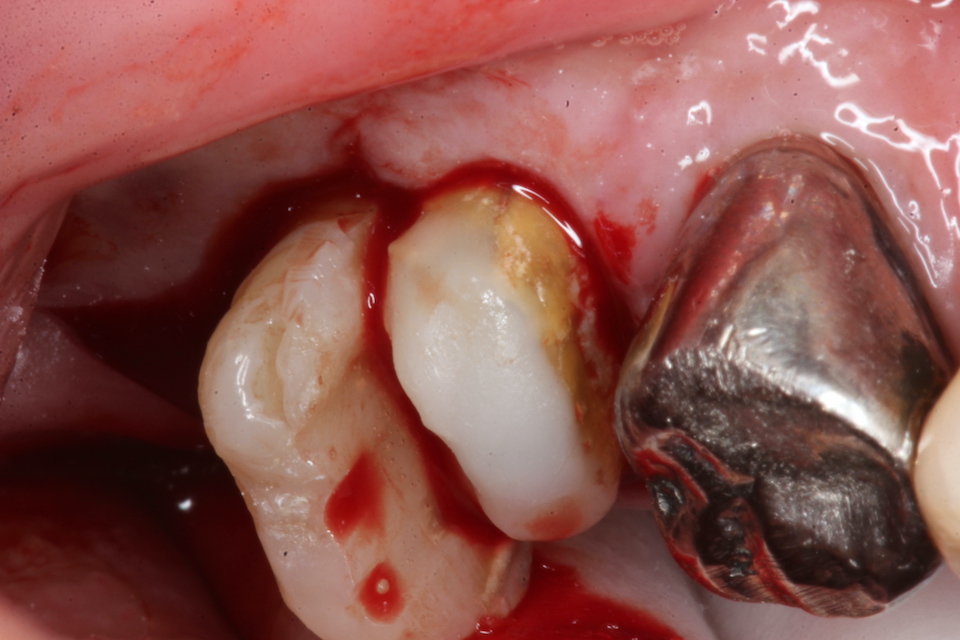

70代男性、左下7、歯根破折、自発痛++

今日は破折した歯根の接着面を新鮮面を出しきれいにしてスーパーボンドの筆積み法で貼り合わせポストを入れてCR併用で再建し、抜歯窩に挿入固定するだけだ。

以下時系列でどうぞ

根管充填材と歯質との間には隙間が存在し、細菌の代謝産物の黒色物質のFeSで覆われている。緊密な充填など絵に描いた餅にすぎない。

遠心根の切断面もスーパーボンド+CRで覆っておく